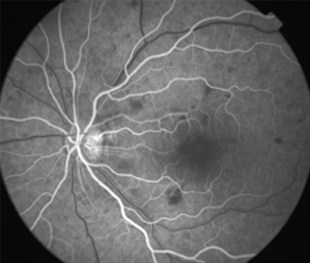

Angiografía OD

Angiografía OI

- Angiografía: teñido arterial, escape capilar, más tardíamente, no perfusion arteriolar y venular con teñido de las paredes vasculares y dilatación venosa.